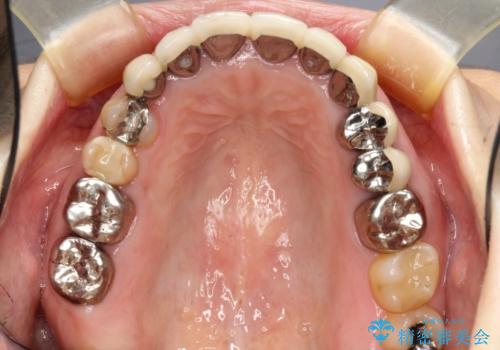

取り急ぎ下顎前歯数歯の根管治療を、銀座しらゆり歯科医院長の林先生にお願いし、それ以外に気になっている、不自然な色調のクラウン、金属部分が見えてブラッシングがしにくいインプラント補綴、口元の突出感、出血のしやすい歯周ポケットなど、全てを解決するための治療を行うこととしました。